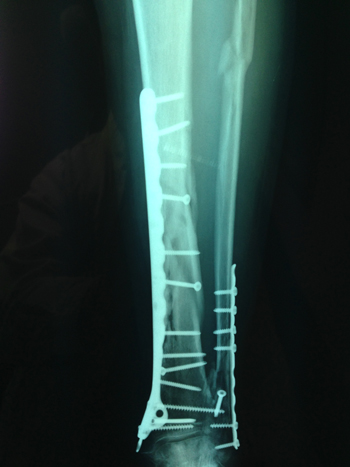

| Συντριπτικό κάταγμα κνήμης περόνης | Συντριπτικό κάταγμα κνήμης περόνης |